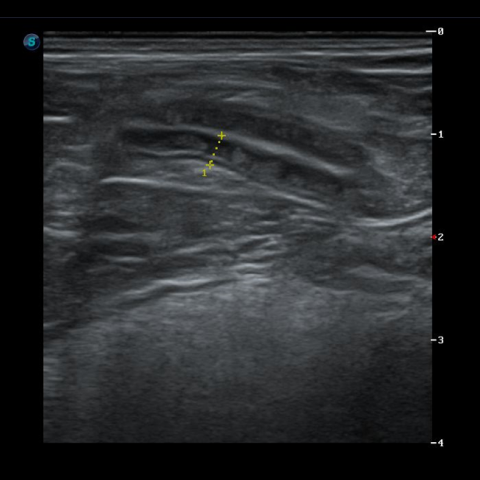

°¢ »óȲ¿¡ ¸ÂÃç ºÐº¯°Ë»ç, Ç÷¾×°Ë»ç, ¹æ»ç¼±°Ë»ç, ÃÊÀ½ÆÄ °Ë»ç¸¦ ÁøÇàÇÕ´Ï´Ù.